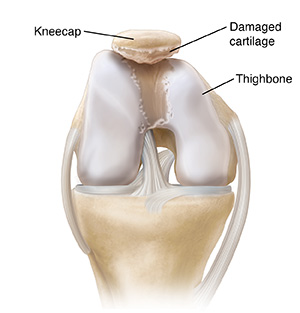

Cartilage damage

Sometimes the cartilage on the back of the kneecap or in the groove of the thighbone is damaged. Damaged cartilage can’t spread pressure evenly. Uneven pressure wears down the cartilage even more.